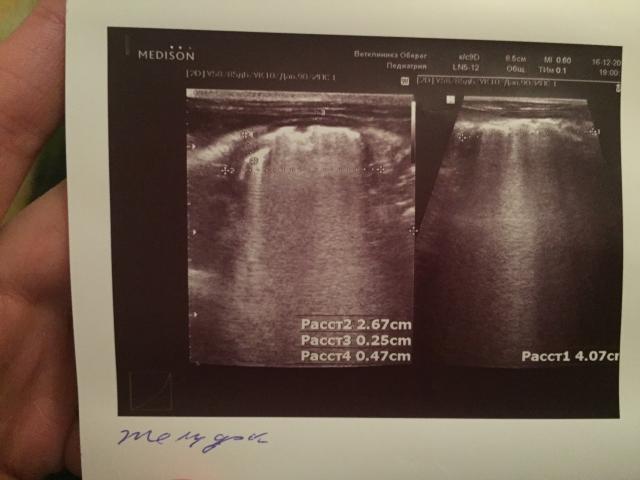

Если можно, то немного подробнее. На основании чего вам поставили такой диагноз, только на основании проведенного УЗИ? Может быть, собаке брали какие-то анализы? Если да, то выложите, пожалуйста, здесь их результаты. Если только данные УЗИ, то это разговор ни о чем (я имею ввиду панкреатит). Гастрит по данным УЗИ вообще не ставят.

К сожалению, ничего не могу рассмотреть. Попробуйте сами прочесть описание с фото. Если сможете, сделайте снимок более качественным. Или можно снять крупнее по частям. Может быть, тогда буквы будут видны более четко.

Спасибо, фотографии четкие. Я все прочитал. Как я и думал, там и "не пахнет" никаким гастродуоденитом, а тем более, панкреатитом.